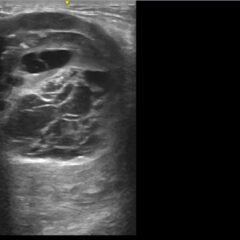

This is a case of a 35-year-old postpartum female presenting to the emergency department (ED) with acute onset chest pain and dyspnea with initial concern for acute ST-segment elevation myocardial infarct (STEMI). Her electrocardiogram (ECG) showed ST segment elevations in the lateral leads and inferior leads with depressions in the high lateral and septal leads. Given her post-partum status, spontaneous coronary artery dissection (SCAD) was part of the differential as well as other emergent processes. Upon cardiac catheterization, the patient was found to have 50% vasospasm in the left circumflex coronary artery. Her post-catheterization echocardiogram showed a normal ejection fraction (EF) without regional wall abnormalities. This is an interesting case of chest pain in a younger patient, without typical acute coronary syndrome (ACS) risk factors, presenting with a concerning ECG likely due to coronary vasospasm. We will discuss other atypical causes of STEMI patterns that should be considered in the differential and management of such patients.